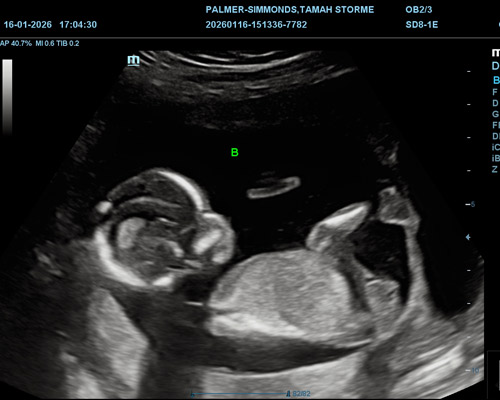

Expecting twins brings a unique kind of excitement, along with more questions and curiosity along the way. Seeing both babies together during a scan can be a special and emotional experience for many parents.

A twin scan near Wakefield, at Baby Bump, allows the sonographer to carefully observe both babies and check how they are developing side by side. Because there are two babies, the scan is carried out with extra attention to detail to ensure both are clearly assessed.

During the ultrasound, several important aspects are reviewed, including the presence of both babies, their heartbeats, positioning, and general progress. This helps provide reassurance while also giving parents a chance to see both babies moving on screen at the same time.

For many families, this moment becomes one of the highlights of the journey, offering both reassurance and a strong sense of connection.